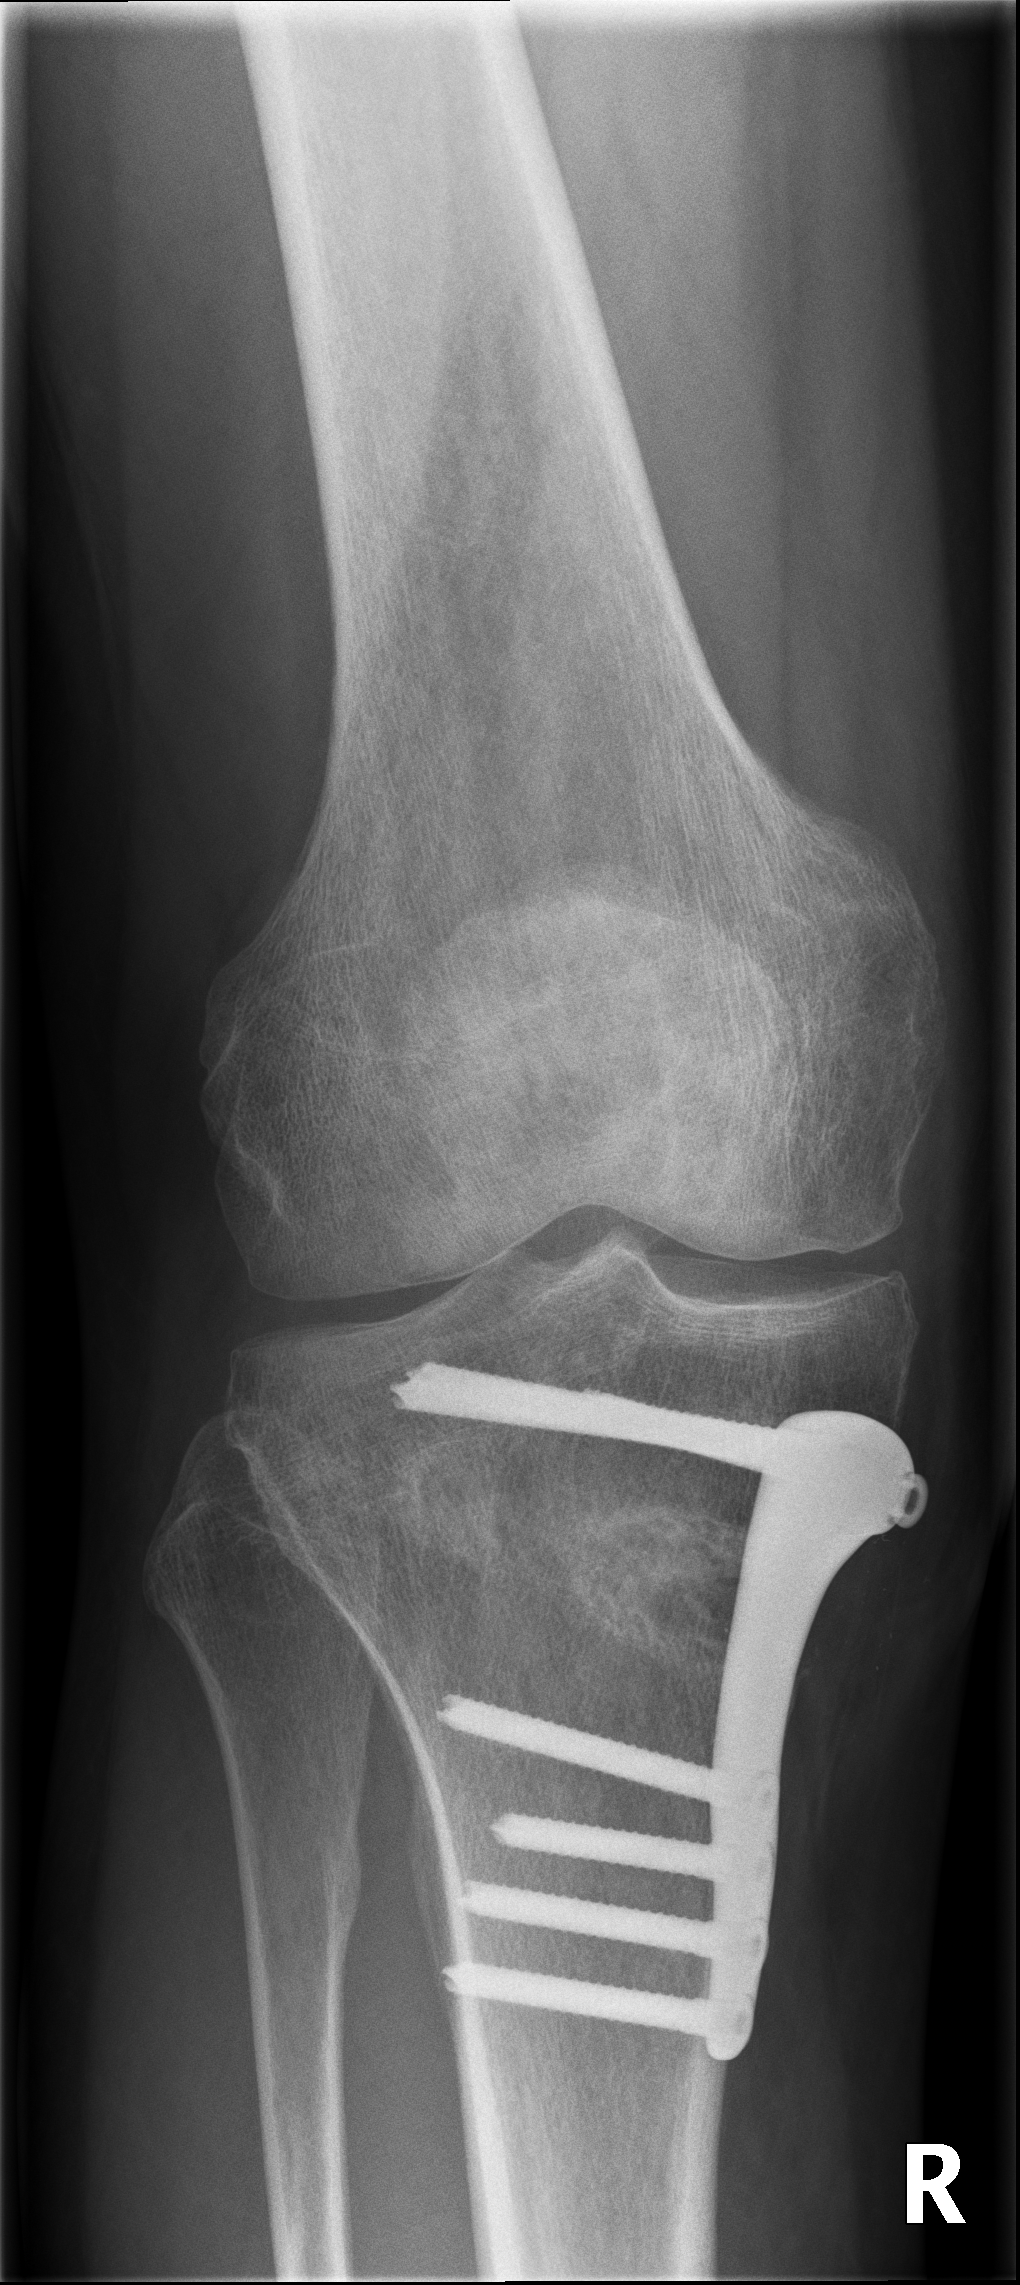

Bei innenseitigen Knorpelschäden mit Fehlstellung am Schienbein ist eine Hohe tibiale Osteotomie (HTO, high tibial osteotomy) sinnvoll. Dabei wird im Bereich des Schienbeinkopfes ein Schnitt durchgeführt und dieser Spalt danach aufgeklappt um die Beinachse zu korrigieren. Die Stellung wird mittels Platte fixiert.

Unten: Knöcherne Heilung des aufgeklappten Spaltes nach 5 Monaten.